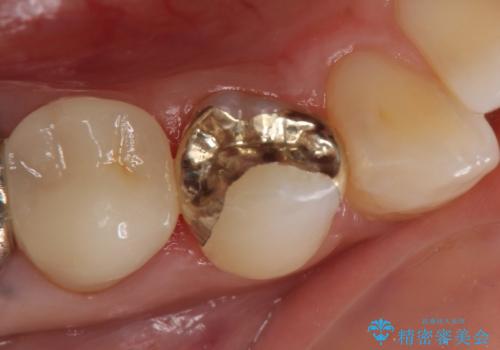

古い銀歯と虫歯を除去後、PGA(ゴールド)インレーによる修復を行いました。

ゴールドは化学的な安定性が高いため変色や腐食がほとんどなく、アレルギーなども起こりにくい人体に優しい素材です。

また硬さも天然歯に近いため周囲の歯への影響も少なく、さらに適合もよいため虫歯の再発も少ない、とても補綴に適した材料です。